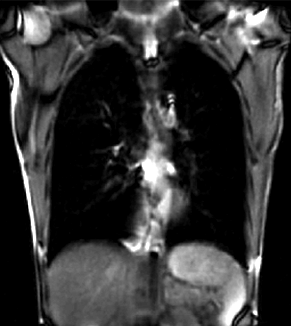

Slicer Registration Library Case #46: 2D Cine MRI of Breathing Cycle

| fixed image/target | moving image |

- reference/fixed : 2D coronal MRI 256x256 , FIESTA sequence ,1.5 x 1.5 x 15mm voxel size

- moving: 2D coronal time series, 200 images total, each as fixed above